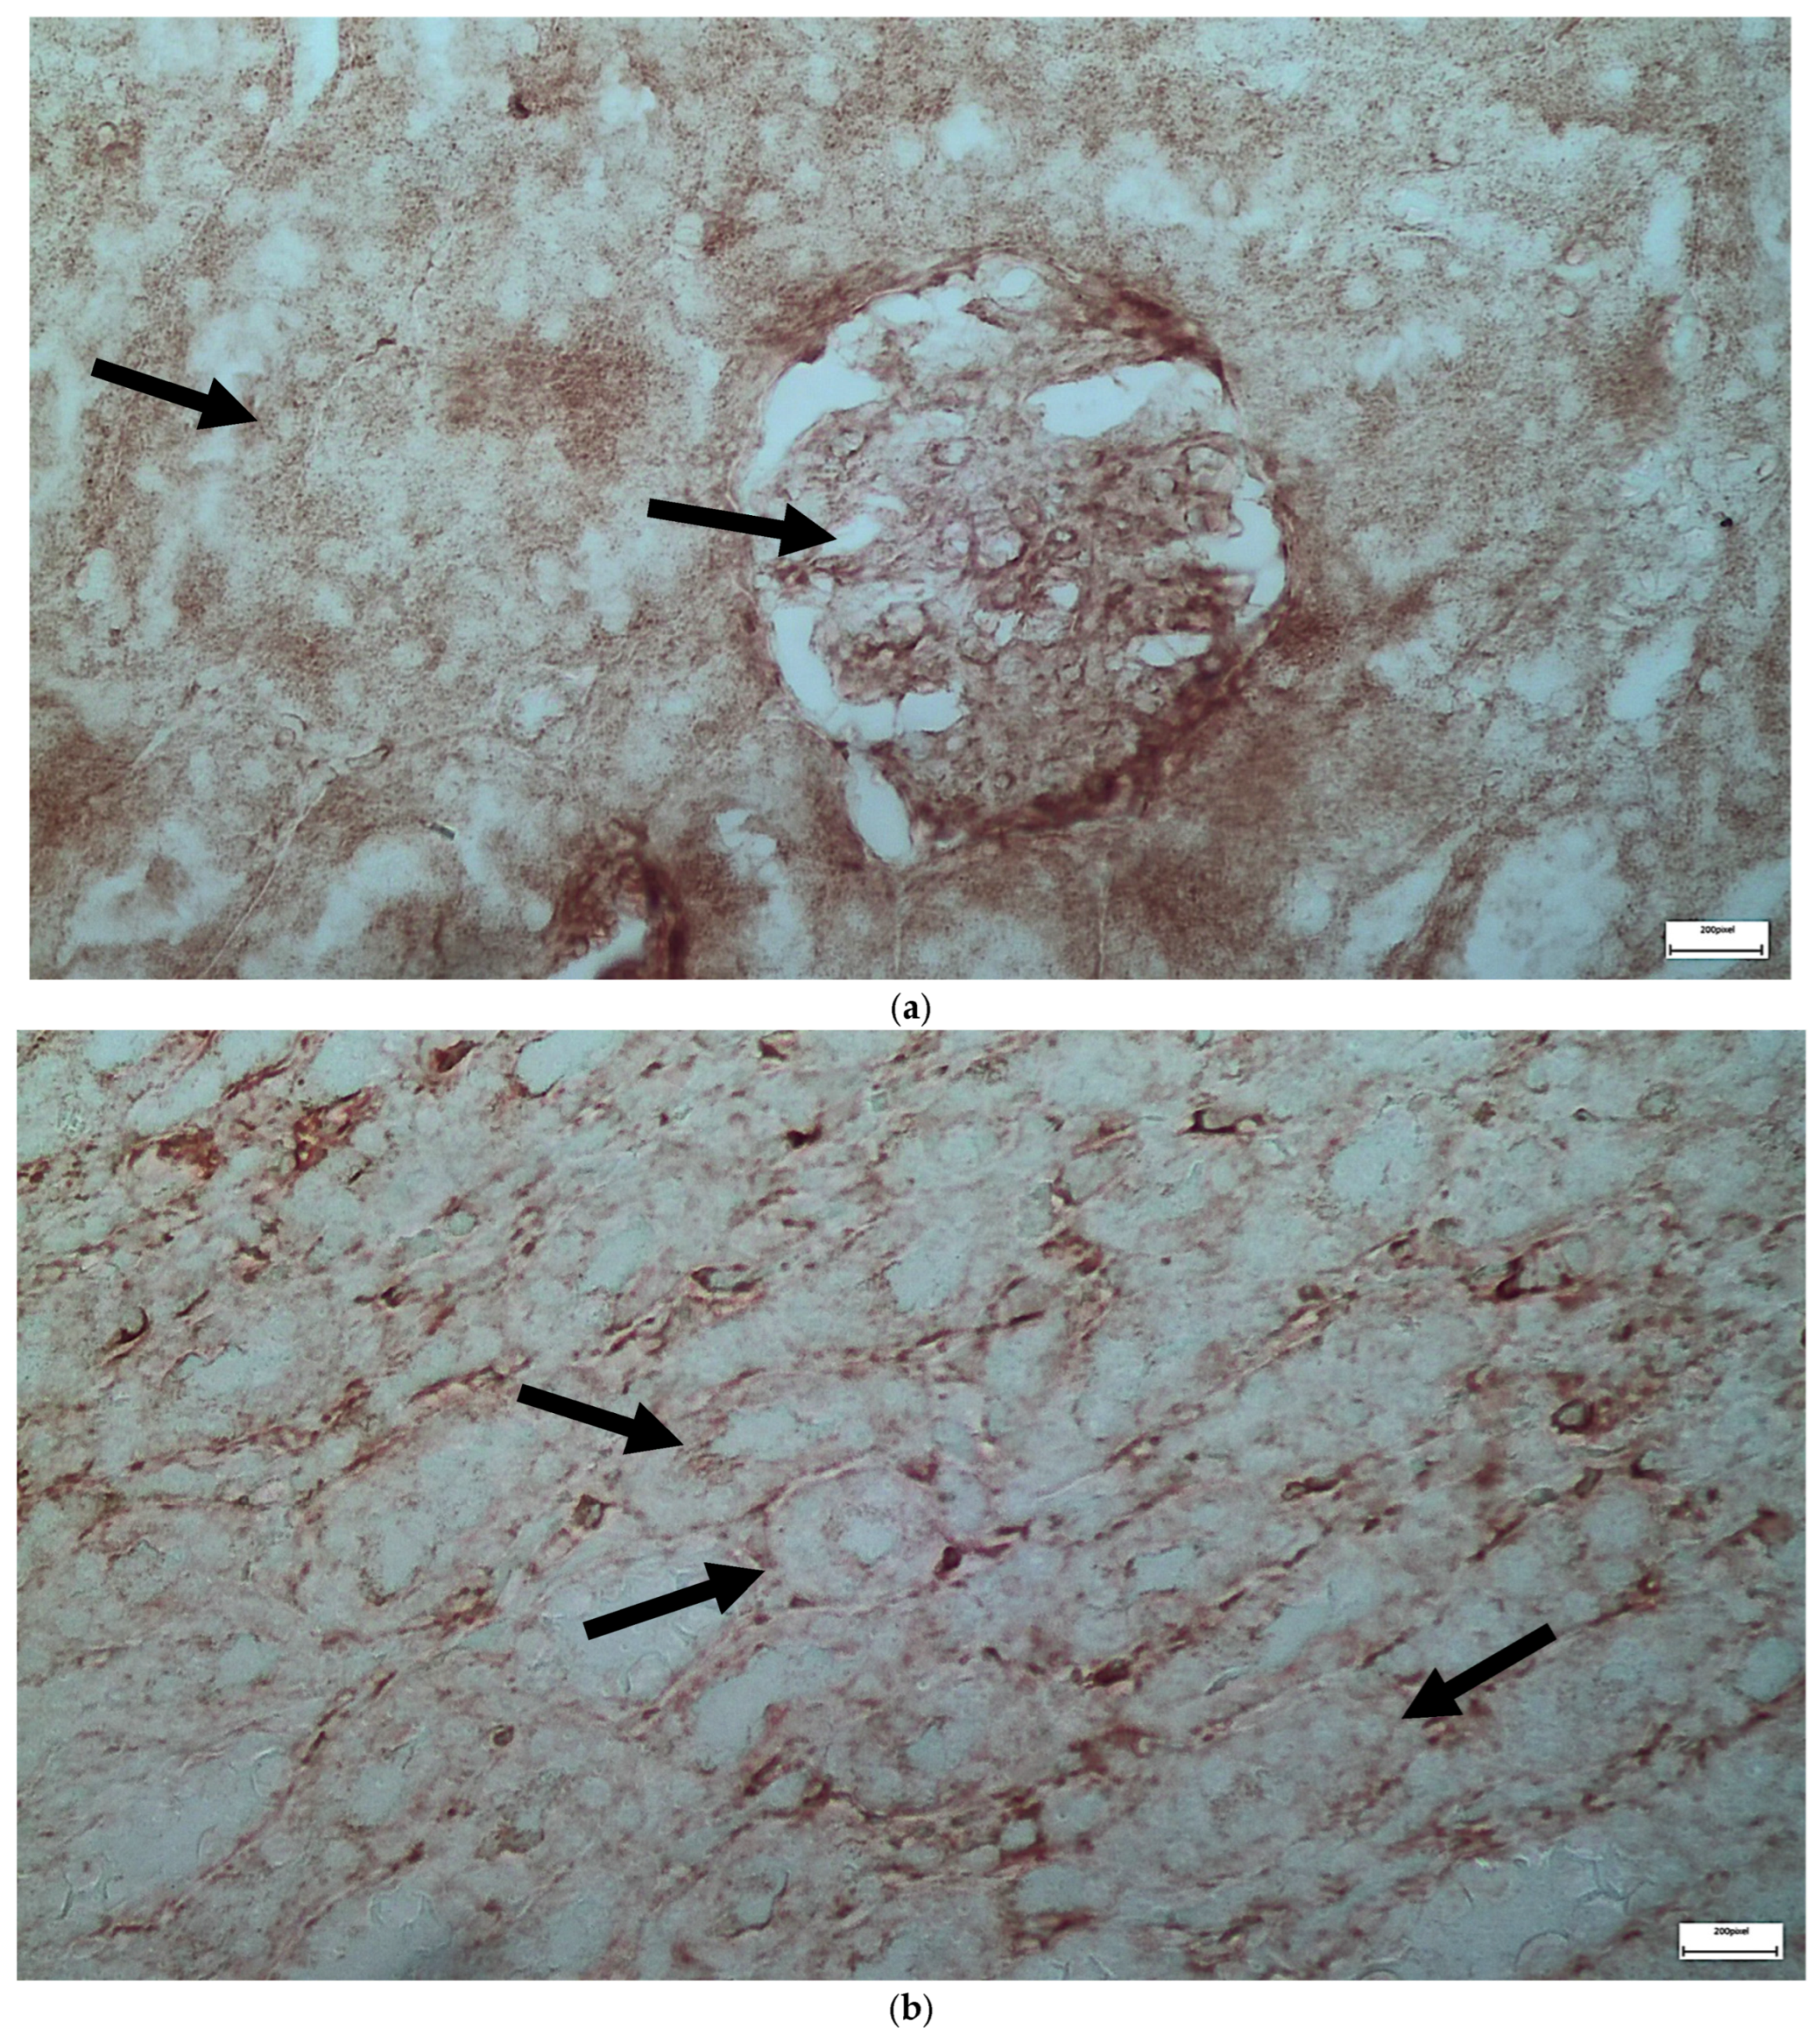

| C | Renal tubules and corpuscles | IL-6 | 1 | 2 | 2 |

| C | Renal tubules and corpuscles | EGFR | 1 | 1 | 1 |

| V1 | Renal tubules | IL-6 | 2 | 4 | 8 |

| V1 | Renal corpuscles | IL-6 | 2 | 2 | 4 |

| V1 | Renal tubules | EGFR | 3 | 4 | 12 |

| V1 | Renal corpuscles | EGFR | 2 | 2 | 4 |

| V2 | Renal corpuscles | IL-6 | 2 | 1 | 2 |

| V2 | Renal tubules | IL-6 | 2 | 3 | 6 |

| V2 | Renal corpuscles | EGFR | 3 | 4 | 12 |

| V2 | Renal tubules | EGFR | 2 | 4 | 8 |

| M1 | Renal corpuscles | IL-6 | 2 | 3 | 6 |

| M1 | Renal tubules | IL-6 | 2 | 1 | 2 |

| M1 | Renal corpuscles | EGFR | 3 | 4 | 12 |

| M1 | Renal tubules | EGFR | 1 | 2 | 2 |

| M2 | Renal corpuscles | IL-6 | 3 | 3 | 9 |

| M2 | Renal tubules | IL-6 | 2 | 3 | 6 |

| M2 | Renal corpuscles | EGFR | 1 | 2 | 2 |

| M2 | Renal tubules | EGFR | 1 | 3 | 3 |

| VM | Renal corpuscles | IL-6 | 3 | 4 | 12 |

| VM | Renal tubules | IL-6 | 1 | 2 | 2 |

| VM | Renal corpuscles | EGFR | 3 | 3 | 9 |

| VM | Renal tubules | EGFR | 2 | 3 | 6 |

| IL-6 | Renal Tubules | 2 (1–4) | 3 (1–5) | 3 (2–5) | 5 (3–6) | 0.048 | VM > C (p = 0.03) |

| Renal Corpuscles | 1 (0–3) | 2 (1–4) | 4 (2–5) | 5 (3–6) | 0.0089 | VM > C (p = 0.006), M > C (p = 0.049) | |

| EGFR | Renal Tubules | 3 (2–4) | 5 (3–6) | 4 (3–6) | 6 (5–7) | 0.0197 | VM > C (p = 0.012), V > C (p = 0.043) |

| Renal Corpuscles | 3 (2–4) | 4 (3–5) | 5 (4–6) | 6 (5–7) | 0.0247 | VM > C (p = 0.013), M > C (p = 0.038) |